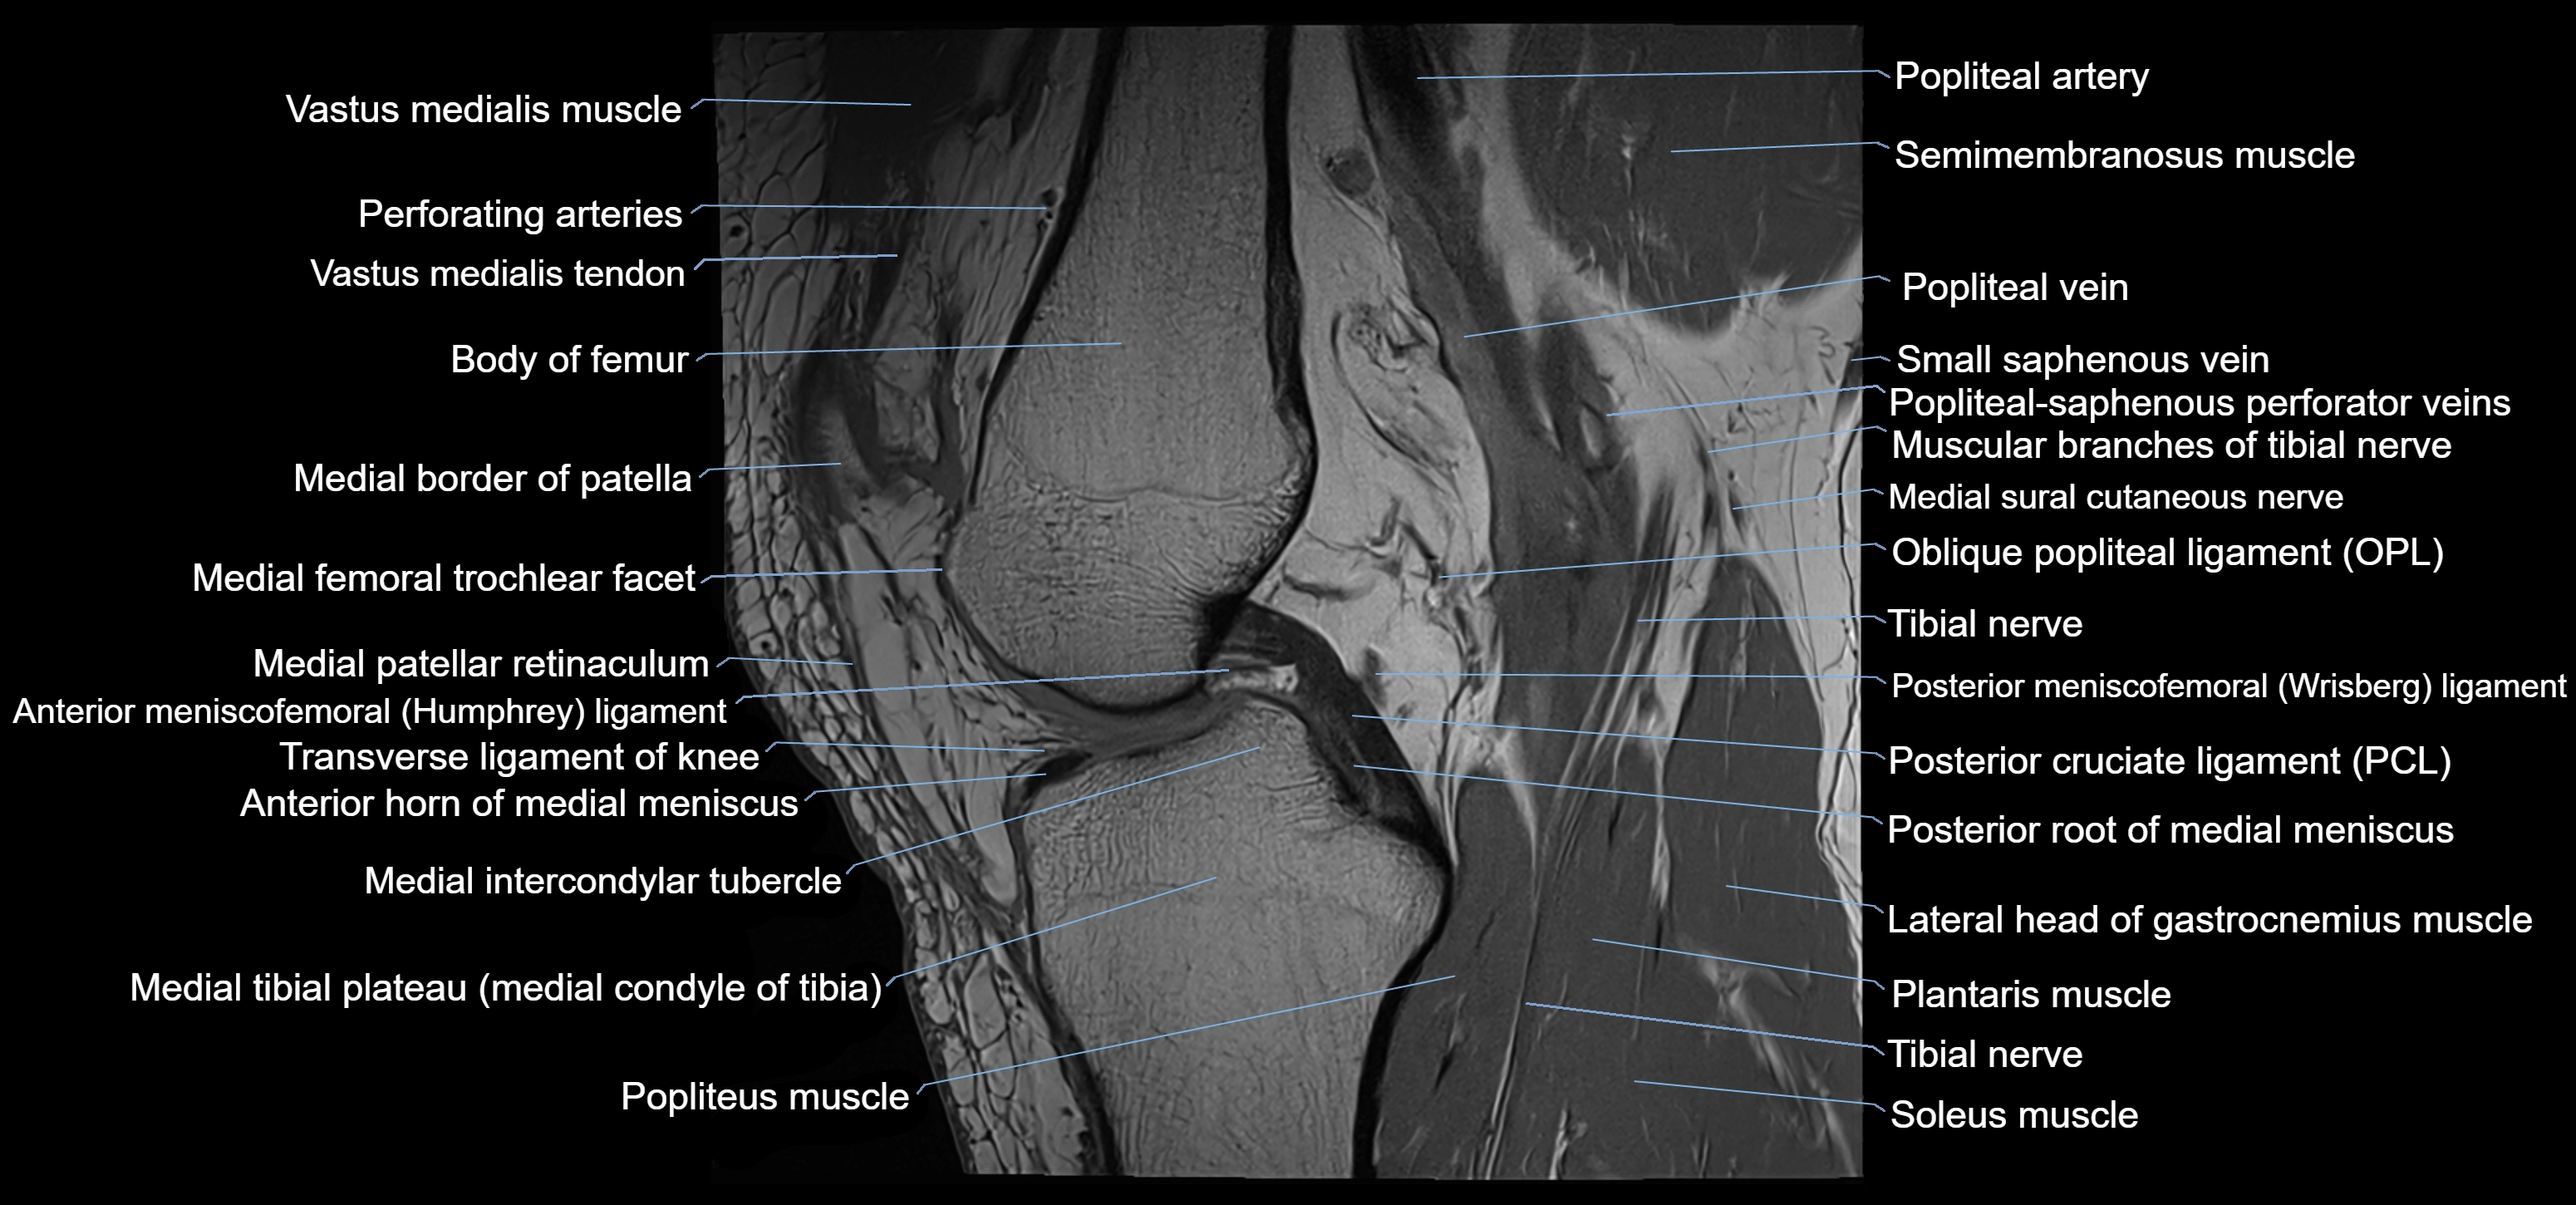

- Anterior horn of medial meniscus

- Anterior meniscofemoral ligament

- Body of medial meniscus

- Distal vastus medialis tendon

- Lateral head of gastrocnemius muscle

- Medial condyle of femur

- Medial condyle of tibia

- Medial epicondyle of femur

- Medial gastrocnemius tendon

- Medial head of gastrocnemius muscle

- Medial intercondylar tubercle

- Medial meniscus

- Medial patellar retinaculum

- Medial tibial plateau

- Muscular branches of tibial nerve

- Oblique popliteal ligament

- Patella

- Patellar tendon (patellar ligament)

- Perforating Arteries (Knee joint)

- Popliteal artery

- Popliteal vein

- Popliteal–Saphenous perforating veins

- Popliteus muscle

- Posterior cruciate ligament

- Posterior horn of medial meniscus

- Posterior meniscofemoral ligament

- Posterior root of medial meniscus

- Semimembranosus muscle

- Small saphenous vein

- Soleus muscle

- Tibia

- Tibial nerve

- Transverse ligament of knee

- Vastus medialis muscle